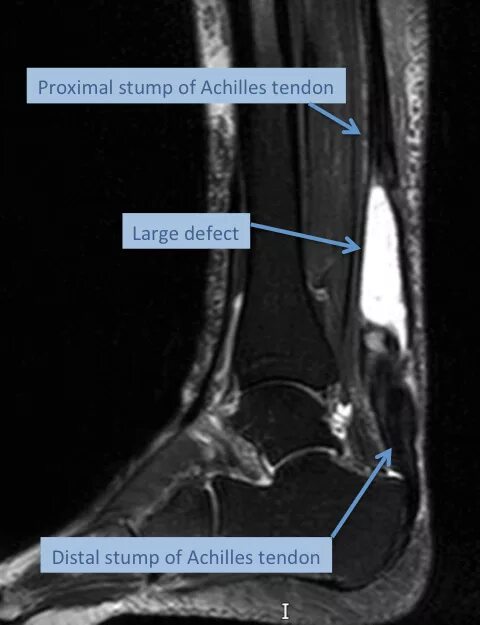

Мрт ахиллового сухожилия